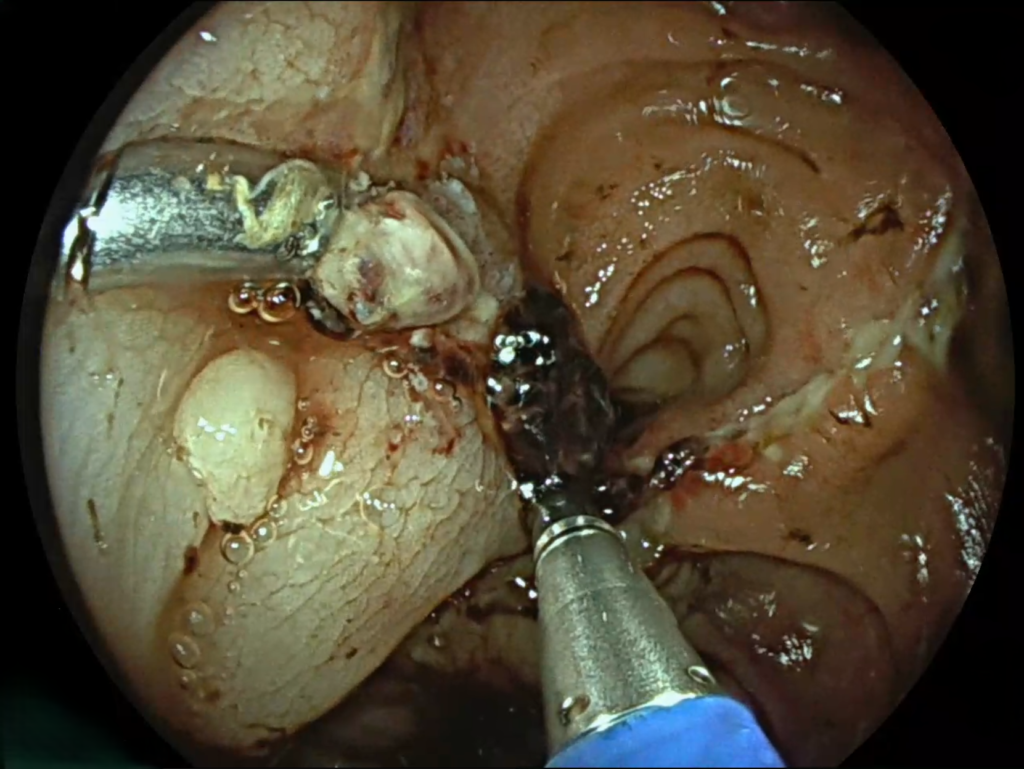

Inițial, evoluția postoperatorie a fost favorabilă. Totuși, pacientul a dezvoltat o hemoragie digestivă inferioară, gestionată prompt prin hemostază endoscopică de urgență de către dr. David Marica, în contextual nevoii constante de hemodializă.